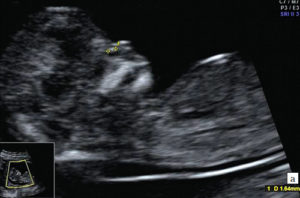

2. Гипоплазия носовой кости. УЗИ сделано на 12 неделе беременности. Длина — 1,4 мм (ниже границы нормы).

Размеры носовых костей плода зависят от срока беременности. Так, например, на 12–13 неделе беременности длина носовой кости всего лишь 3,0 мм. На 20–21 неделе она увеличивается до 5, 5 — 5,7 мм, а к 35 неделе беременности достигает 9,0 мм.

Для того чтобы правильно и точно оценить параметры носовой кости, полученные во время проведения ультразвукового исследования, врач должен обладать большим опытом и высокой квалификацией. Помимо этого необходимо чтобы УЗИ проводилось на современном аппарате — в противном случае получение достоверных результатов очень сомнительно.